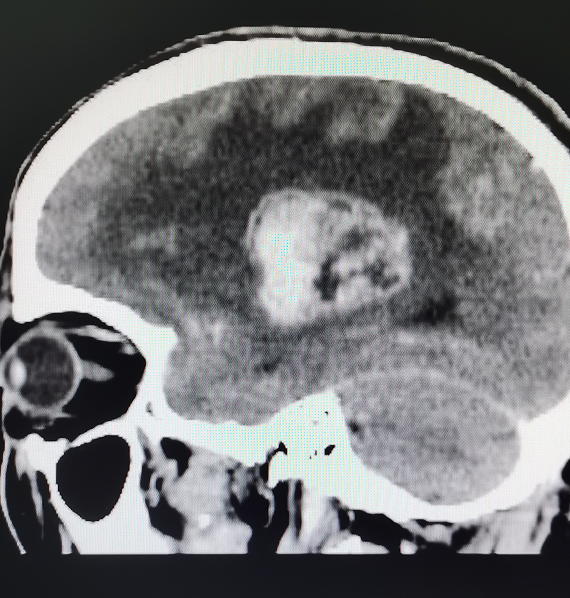

肿瘤质地异常坚硬,是一种非常罕见的脑肿瘤病理类型(见图2),难以像普通胶质瘤那样分块切除(经过总院病理检查最终诊断是很罕见的病理类型:胶质肉瘤),但手术团队凭借成熟的手术技能,经过4个多小时,成功解决手术中遇到的种种难题,将肿瘤包裹的血管分离开,保护语言、肢体运动功能区,并且将肿瘤精准成功全部切除,瘤床也获得精确彻底止血。

图2.手术标本及术后病理检查结果为罕见的脑膜型胶质肉瘤